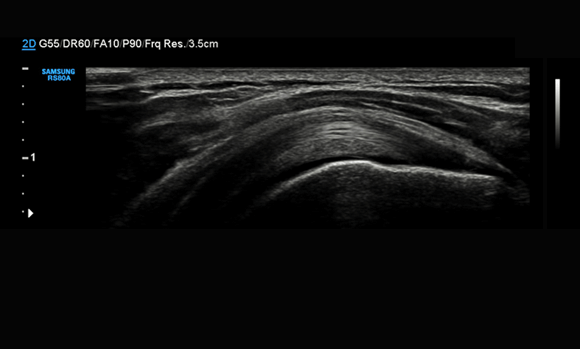

LM4-15B

Applications:

Small parts, Vascular, Musculoskeletal

LA4-18B

L3-12A

LA3-16A

LA3-16AI

Musculoskeletal